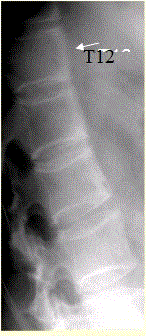

问题 患者男,35岁,外伤后行腰椎CR检查,结果如下图。 观察此张X线片,正确的是

选项 A.所示椎体未见异常 B.T12、L1、L2椎体前缘毛糙 C.L1椎体可疑压缩性骨折 D.所见椎体密度增高 E.所见椎体密度减低 F.建议CT检查,观察椎小关节及骶髂关节 G.建议MRI检查,观察椎体有无异常

答案 BFG